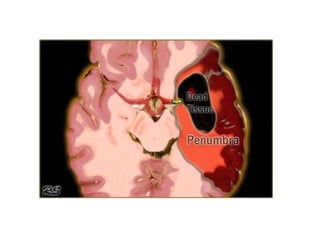

• In the absence of blood flow, available energy can maintain

neuronal viability for 2-3 minutes

• In the brain, ischemia is incomplete, with collateral supply

• Cerebral ischemia = central irreversibly infarcted tissue core

surrounded by peripheral region of stunned cells, the

‘penumbra’

• The penumbra is potentially salvageable with early

recannalization

• With CT and MR-diffusion we can get a good impression of

the area that is infarcted.

• But, we cannot preclude a large ischemic penumbra (tissue

at risk).

• With perfusion studies we monitor the first pass of an

iodinated contrast agent bolus through the cerebral

vasculature.

• Areas of decreased perfusion will tell us which area is at

risk.

• Infarct shows:

– Severely decreased CBF (< 30%) and CBV (<40%)

with increased MTT

• Penumbra shows either:

– Increased MTT, moderately decreased CBF and

normal or increased CBV

– Increased MTT, markedly decreased CBF and

moderately reduced CBV

Core and Penumbra